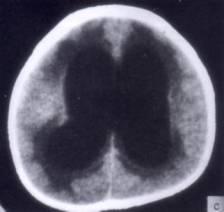

问题 病历摘要:??患者女性,10岁。结核性脑膜炎愈后8月,头痛伴恶心呕吐1周,并渐加重。体检:神清,精神差,反应迟钝,双眼底视神经乳头水肿,双眼外展差,余未见明显异常。 根据病史、CT,入院诊断考虑下列哪种?

选项 A.梗阻性脑积水 B.交通性脑积水 C.外部性脑积水 D.先天性脑积水 E.耳源性脑积水 F.良性颅内压增高 G.假性脑瘤

答案 B